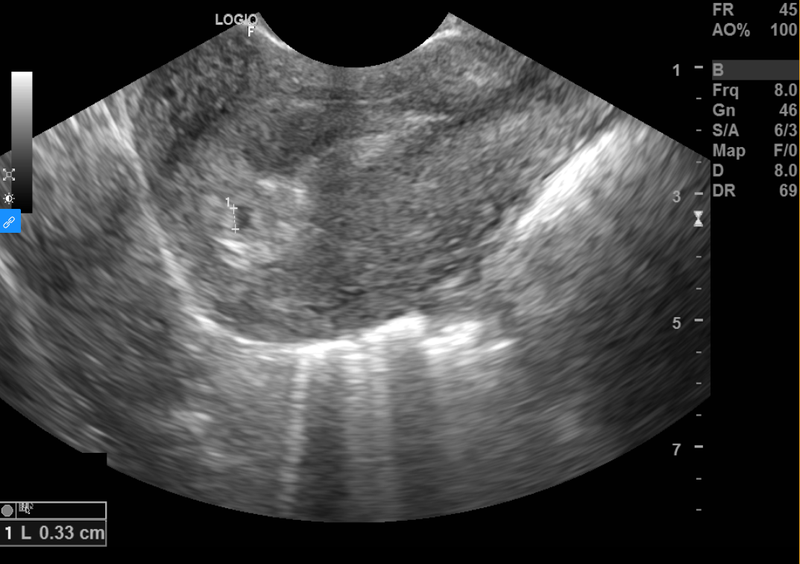

Vậy nên, khi thai ở tuần thứ 2 của thai kỳ, siêu âm sẽ không thấy và kết quả không chính xác vì còn quá sớm. Trường hợp thai đủ 2 tuần tuổi và đã được hình thành thì kích thước thai quá nhỏ nên dù siêu âm qua thành bụng hay siêu âm đầu dò qua âm đạo cũng rất khó để thấy rõ ràng.

Do đó, mẹ bầu nên đợi đến khi thai được từ 6 - 10 tuần tuổi kể từ ngày cuối cùng của kỳ kinh gần nhất, đây là thời điểm lý tưởng nhất để siêu âm. Mặt khác, việc siêu âm thai quá sớm (thai được 2 tuần tuổi) không chỉ cho kết quả không chính xác mà còn gây ảnh hưởng xấu đến thai nhi.